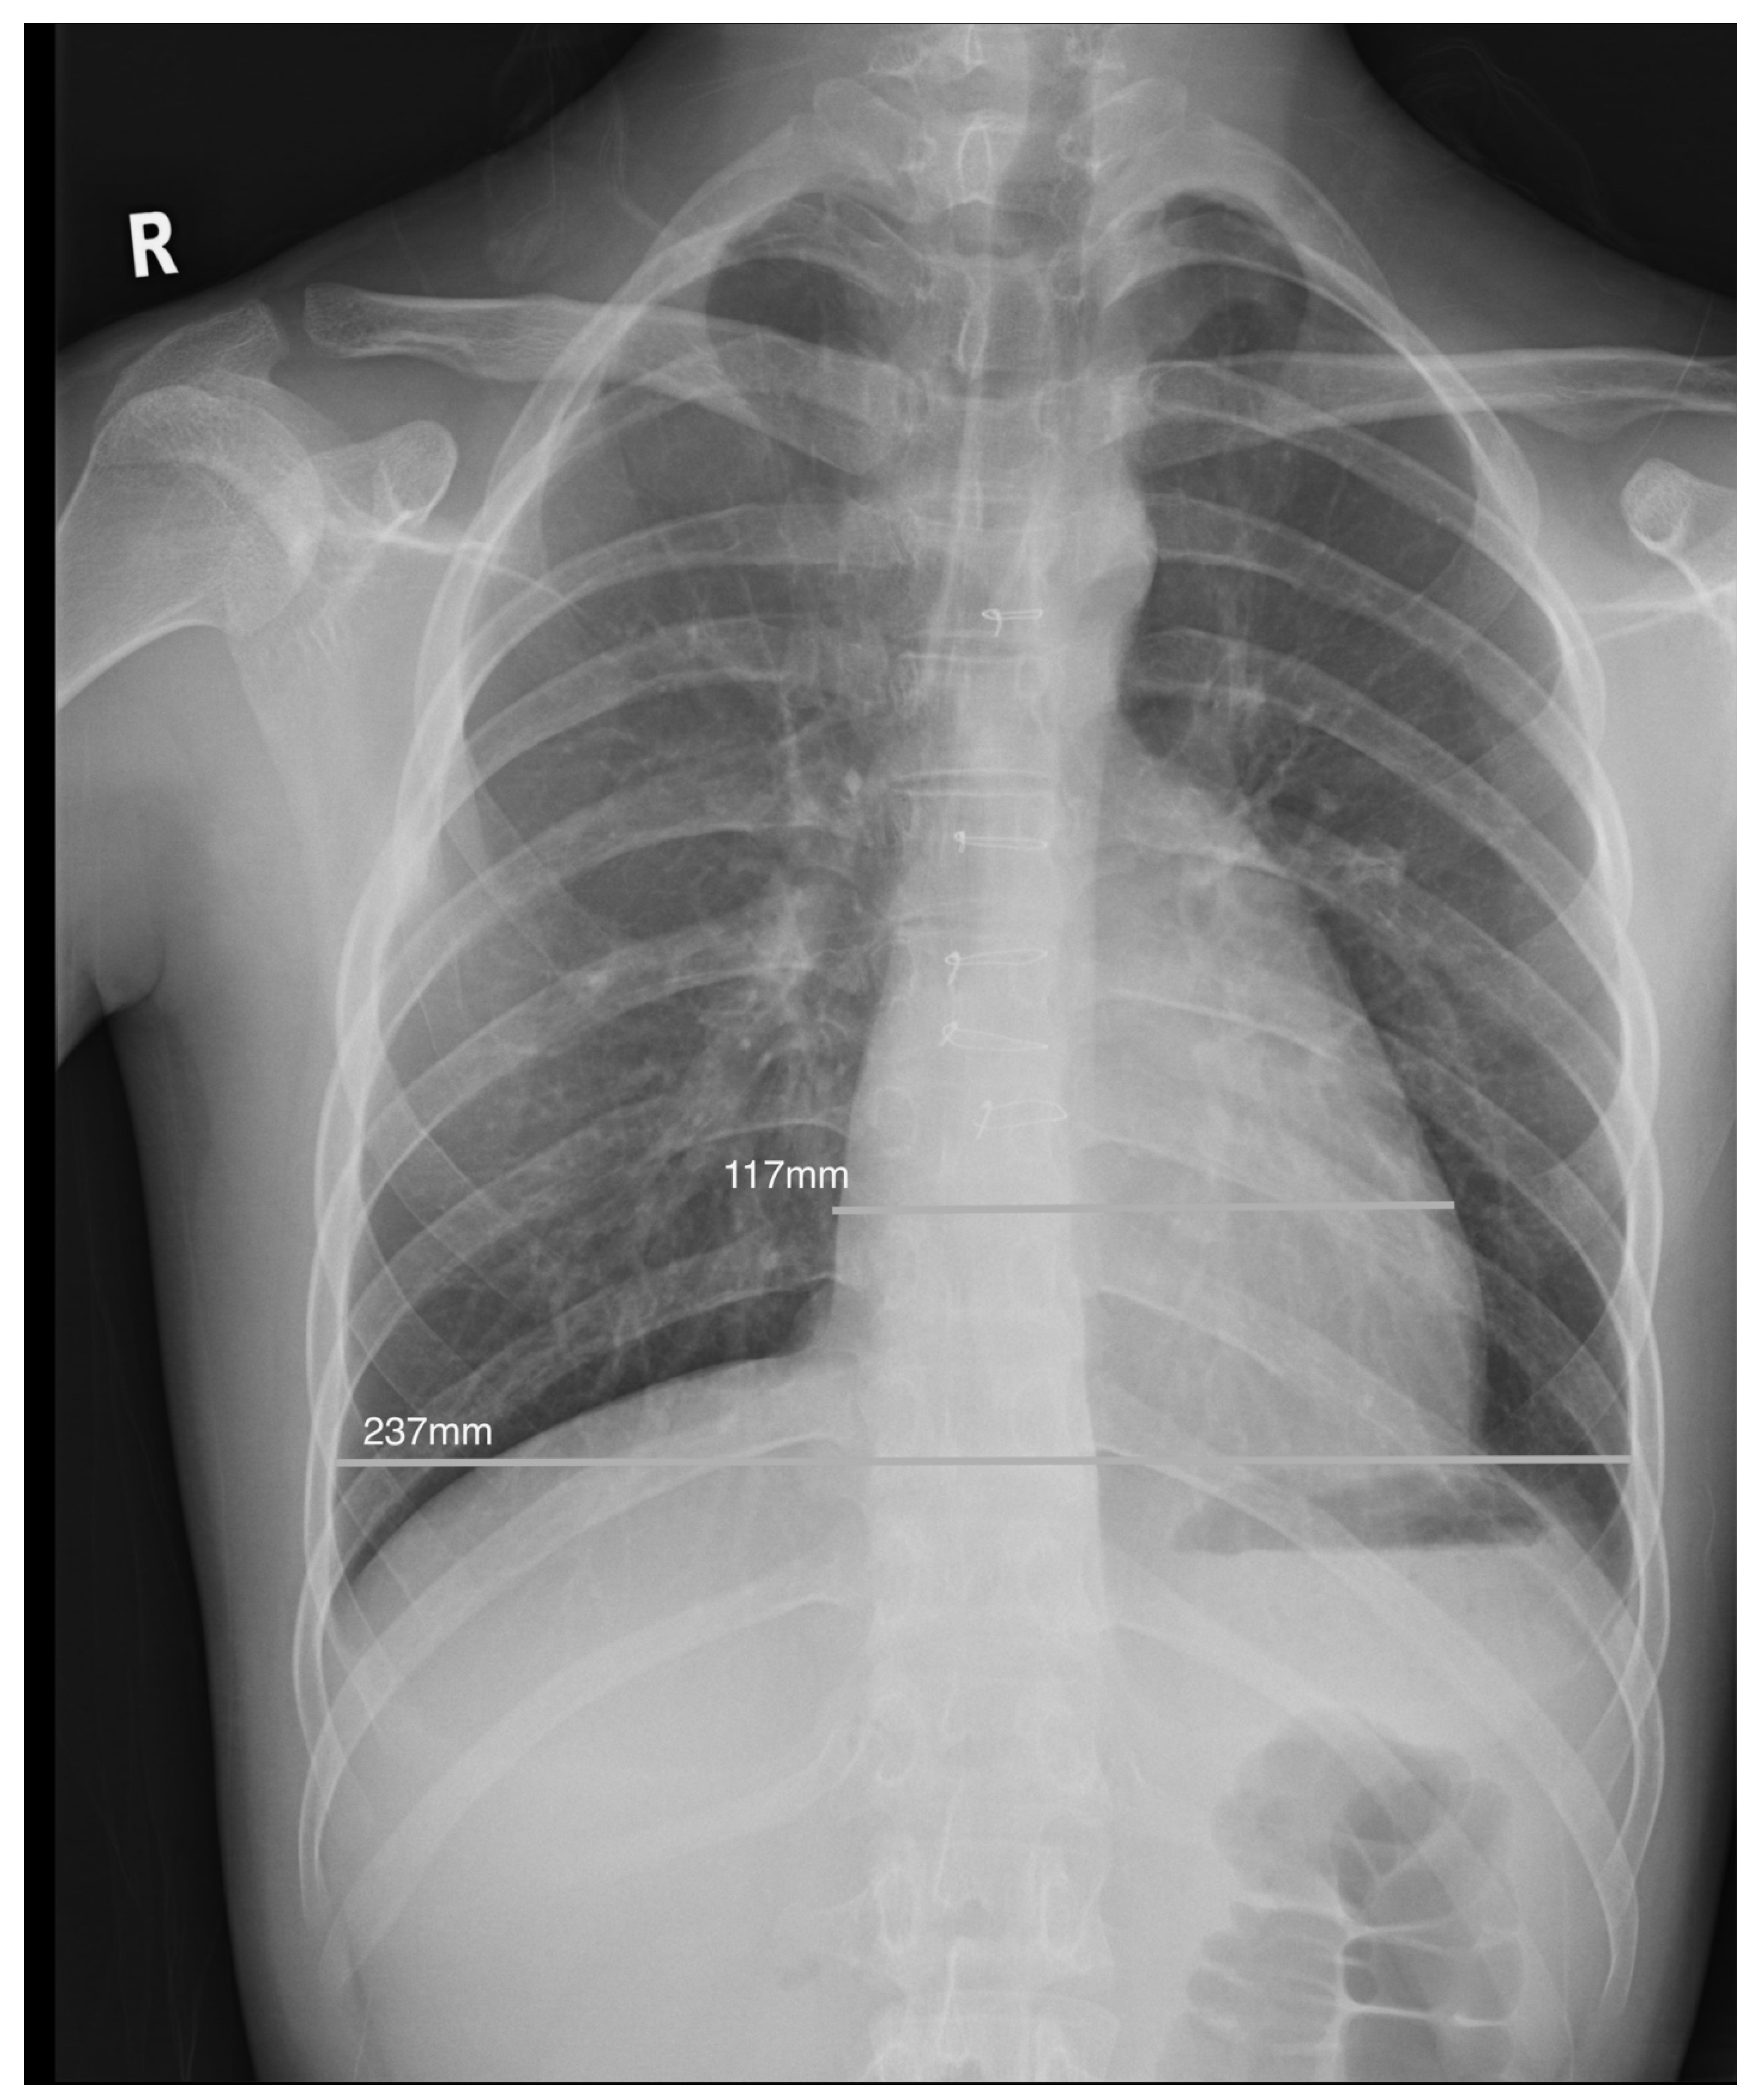

Chest radiographs were evaluated as technically adequate if there were no gross rotational or thoracic abnormalities. All posteroanterior films, regardless of the depth of inspiration, were included. Patients with coexisting lung pathology or pleural effusion where the cardiac silhouette was indistinct were excluded. The CTR was measured as the ratio of the maximal dimension of the cardiac silhouette to the transverse diameter of the rib cage at the level of the right hemidiaphragm using CMS radiology viewer (Fig. 1) and a CTR of >0.5 was defined as abnormal [9]. All measurements of CTR were performed by a single investigator (JPH) who was blinded to the CMR findings.

Figure 1: Illustration of a normal cardiothoracic ratio of 0.49 in an adolescent with increased indexed RV end-diastolic volume of 163 mL/m2 after repair of tetralogy of Fallot.